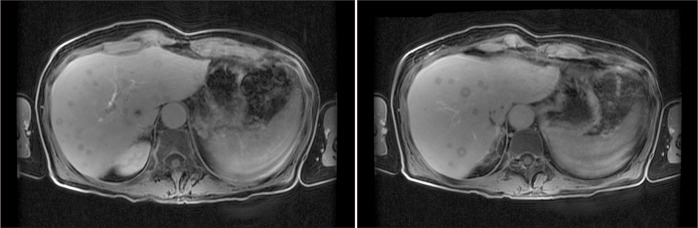

Patients with nonresectable breast cancer liver metastasis (BCLM) face a dismal prognosis. Despite liver transplantation (LT) for metastatic liver tumors having recently shown good results, BCLM represents an absolute contraindication. This study aimed to investigate the potential for long-term survival after LT for BCLMs in a patient experiencing end-stage liver disease, following multiple oncologic treatments. In July 2019, we performed a deceased donor LT on a 41-year-old female with BCLM controlled with human epidermal growth factor receptor 2 targeted therapy, who developed liver failure following multiple locoregional liver-directed treatments. The primary tumor was treated with surgical resection and adjuvant chemoradiation in 2000. The procedure was performed under a protocol approved by the local ethical committee, and by the Italian National Transplant Center. A 12-month treatment with trastuzumab was performed immediately after LT. Immunosuppression following transplantation was undertaken without steroids, and with everolimus. The patient completed 12 months of follow-up without recurrence. Trastuzumab was then withdrawn. Fifteen months after LT, a liver recurrence occurred that was treated with chemotherapy. In October 2021, she developed 2 brain lesions that were treated with stereotactic radiation. The patient is still alive, with a positron emission tomography/computed tomography performed in January 2024 showing no disease. LT for this patient with BCLM of extreme selectivity showed a good clinical outcome. Perioperative systemic treatment and tumor control are necessary. A specific protocol should be discussed within a multidisciplinary team, and with local and national authorities. Even if tumor recurrence occurs, multimodal therapy can control the disease.

Abstract Image